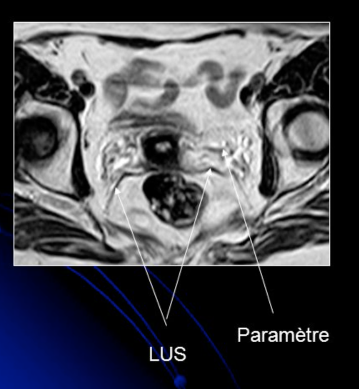

Ligament Rond et Ligament utéro-sacré (LUS)